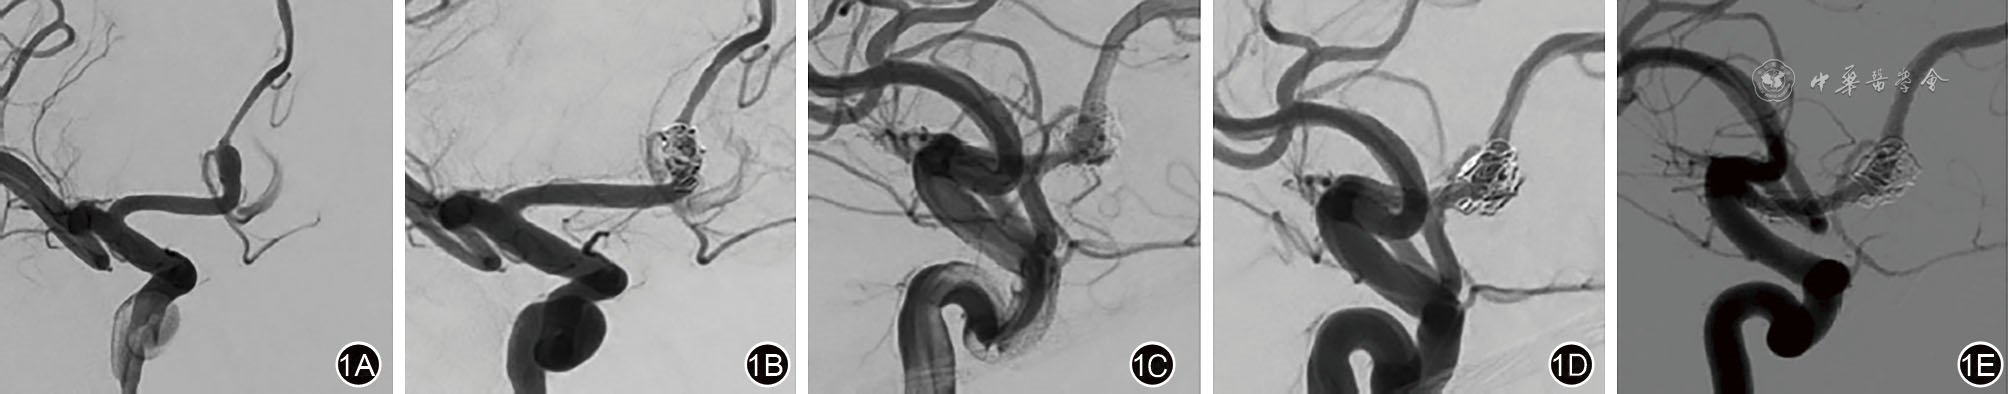

图1 大脑前A2段动脉瘤复发后二期治疗影像学资料 1A:术前右侧颈内动脉DSA示右侧大脑前动脉A2段动脉瘤,累及载瘤动脉的2个分支;1B:使用Neuroform Atlas支架辅助栓塞(载瘤动脉远端纤细,避免编织支架展开不充分或贴壁不良),术后造影示瘤颈少许残留(R-R Ⅱ级);1C:术后6个月行DSA检查示右侧大脑前动脉A2段动脉瘤支架辅助栓塞术后,瘤体残留(R-R Ⅲ级);1D:行复发动脉瘤二期治疗,置入1枚LEO Baby裸支架,术后造影示瘤颈少许残留(R-R Ⅱ级);1E:二期治疗后6个月行DSA检查示支架贴壁良好,动脉瘤完全闭塞(R-R Ⅰ级)。DSA:数字减影血管造影。